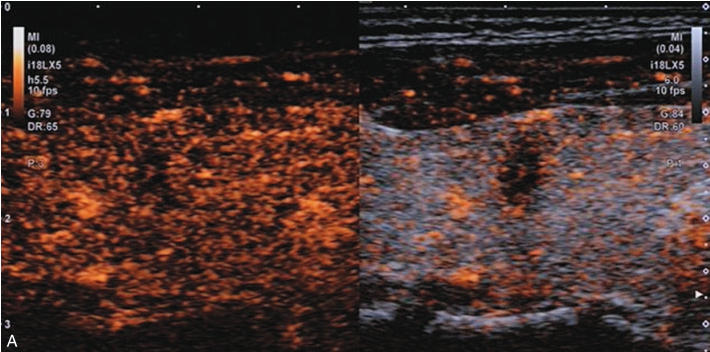

甲状腺形态基本正常,甲状腺实质回声稍增粗,分布尚均匀,甲状腺包膜尚光滑。甲状腺两叶内见多发结节,较大者位于左叶上极,呈类椭圆形,边界清楚,形态规则,纵横比<1,内部回声均匀,未见钙化,后方回声稍增强。CDFI显示左叶较大结节边缘可见丰富的条状血流信号,内部可见条状、点状血流信号,见图1-3-7。

图1-3-7 结节性甲状腺肿常规超声表现

A.常规超声图像;B.CDFI超声图像

甲状腺左叶上极较大结节增强早期呈稍高增强,自结节外周向中央灌注,增强晚期呈等增强,结节内部可见不均匀低增强区,见图1-3-8、ER1-3-4。

图1-3-8 结节性甲状腺肿超声造影图像

ER1-3-4 结节性甲状腺肿的超声造影

甲状腺左叶中部结节15s开始增强。增强早期与周围正常甲状腺组织呈同步等增强,内部增强不均匀,增强后结节边界清,形态规则,周边可见环状高增强,增强晚期呈不均匀性低增强,见图1-3-10、ER1-3-5。

结节性甲状腺肿超声造影表现为病变多与周围正常甲状腺组织呈同步等或高增强,增强多较均匀,伴有囊性变者,内部可见无增强区,增强后结节边界清,周边可见环状增强,增强晚期呈等或稍高增强,也可呈稍低增强。

图1-3-10 结节性甲状腺肿超声造影图

A.增强早期结节呈同步不均匀性等增强;B.增强晚期呈不均匀性低增强